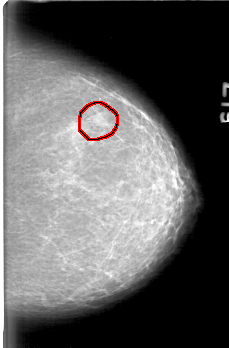

D_4076_1.LEFT_CC

LEFT_CC LINES 5206 PIXELS_PER_LINE 3421 BITS_PER_PIXEL 12 RESOLUTION 43.5 OVERLAY

FILE: D_4076_1.LEFT_CC.OVERLAY

TOTAL_ABNORMALITIES 1

ABNORMALITY 1

LESION_TYPE MASS SHAPE LOBULATED MARGINS OBSCURED

ASSESSMENT 0

SUBTLETY 4

PATHOLOGY BENIGN

TOTAL_OUTLINES 1

BOUNDARY